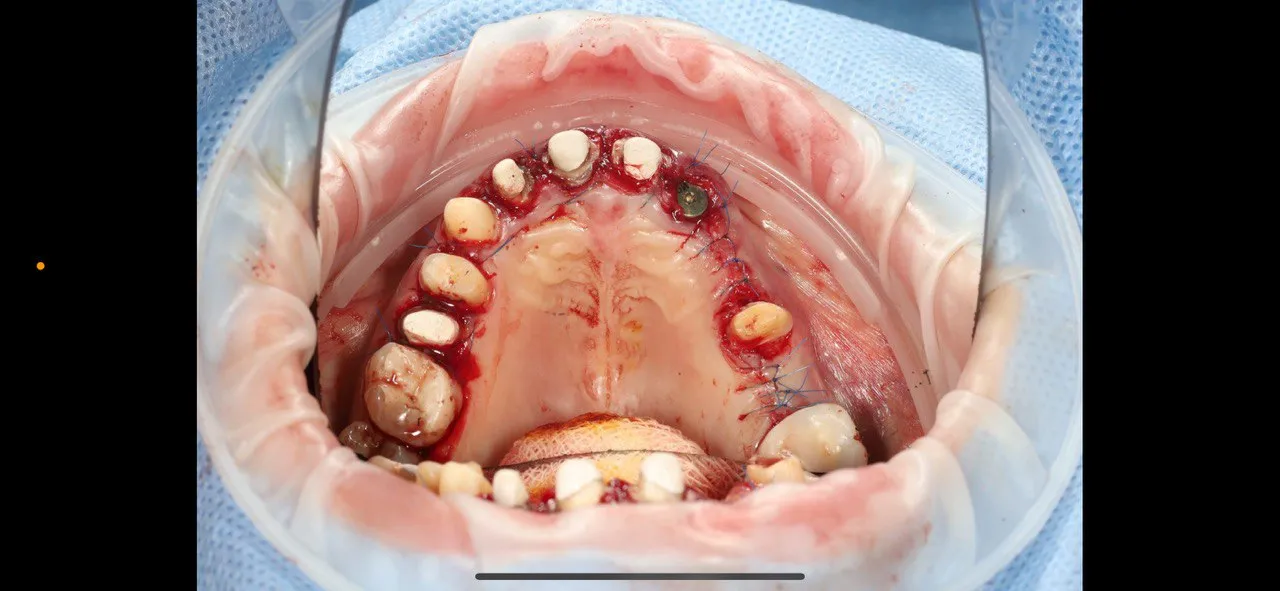

Before-and-after dental implant surgery with guided protocols

Guided implant placement with simultaneous bone augmentation